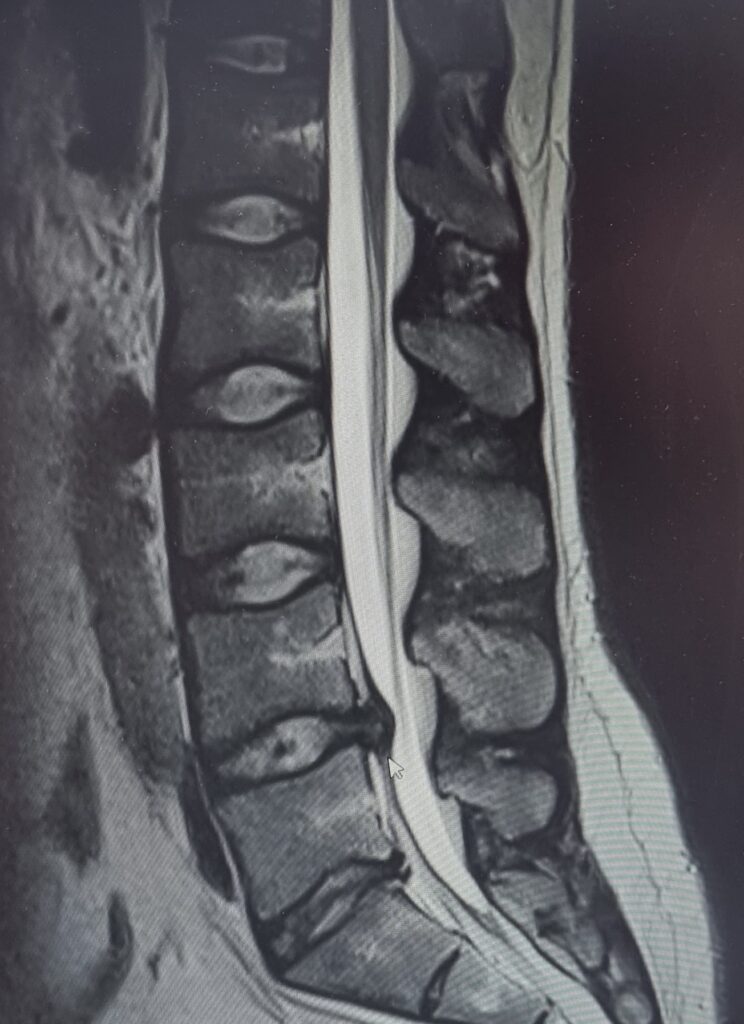

V lednu mi ploténka tzv. vytekla a začala tlačit na kořenový nerv – nemohl jsem ani chodit. Dostal jsem neschopenku, žádanku na MRI a mezitím chodil dva týdny na kapačky proti bolesti. Výsledek ukázal 11mm výhřez se sekvestrem, který tlačil na nerv z pravé strany, a bolest mi vystřelovala z beder až do pravého kotníku. Tohle mě připoutalo na lůžko na 2 měsíce.

Vypadalo to nějak takhle:

výhřez ploténky SM systém Brandýs nad Labem